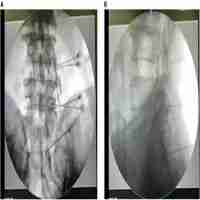

| Abstract | Background: No proof of efficacy, in the form of a randomized controlled trial (RCT), exists to support pulsed radiofrequency (PRF) treatment of the dorsal root ganglion (DRG) for chronic lumbar radicular (CLR) pain. We determined the feasibility of a larger trial (primary objective), and also explored the efficacy of PRF in decreasing pain on a visual analog scale (VAS) and improving the Oswestry Disability Index. Methods: This was a single-center, placebo-controlled, triple-blinded RCT. Patients were randomized to a placebo group (needle placement) or a treatment group (PRF at 42°C for 120 seconds to the DRG). Patients were followed up for 3 months post procedure. Outcomes with regard to pain, Oswestry Disability Index score, and side effects were analyzed on an intention-to-treat basis. Results: Over 15 months, 350 potential patients were identified and 56 were assessed for eligibility. Fifteen of them did not meet the selection criteria. Of the 41 eligible patients, 32 (78%) were recruited. One patient opted out before intervention. Three patients were lost to follow-up at 3 months. Mean VAS differences were not significantly different at 4 weeks (-0.36, 95% confidence interval [CI], -2.29, 1.57) or at 3 months (-0.76, 95% CI, -3.14, 1.61). The difference in mean Oswestry Disability Index score was also not significantly different at 4 weeks (-2%, 95% CI, -14%, 10%) or 3 months (-7%, 95% CI, -21%, 6%). There were no major side effects. Six of 16 patients in the PRF group and three of 15 in the placebo group showed a >50% decrease in VAS score. Conclusion: The recruitment rate was partially successful. At 3 months, the relative success of PRF-DRG was small. A large-scale trial to establish efficacy is not practically feasible considering the small effect size, which would necessitate recruitment of a challengingly large number of participants over a number of years. Until clear parameters for application of PRF are established, clinicians will need to use their individual judgment regarding its clinical applicability, given the present evidence. |